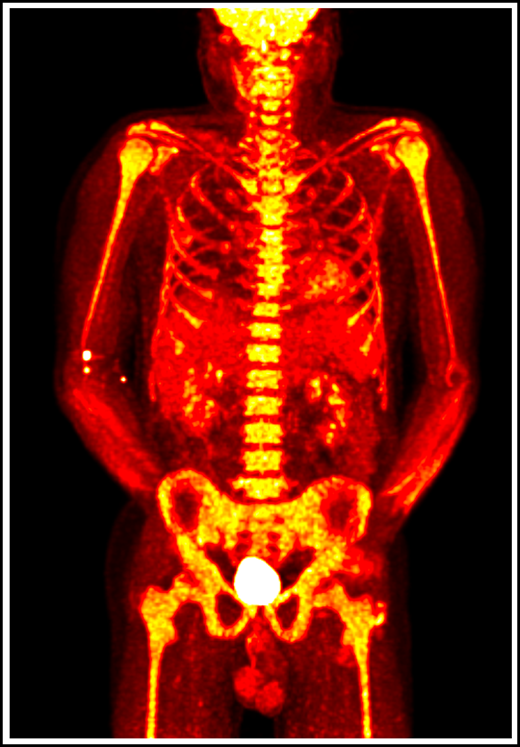

18F-fluorodeoxyglucose positron emission tomography in a patient with VEXAS syndrome demonstrating hypermetabolic activity in bone marrow (yellow). Somatic mutations in UBA1 in hematopoietic cells lead to myeloid-driven inflammation that is often refractory to treatment in patients with VEXAS syndrome.